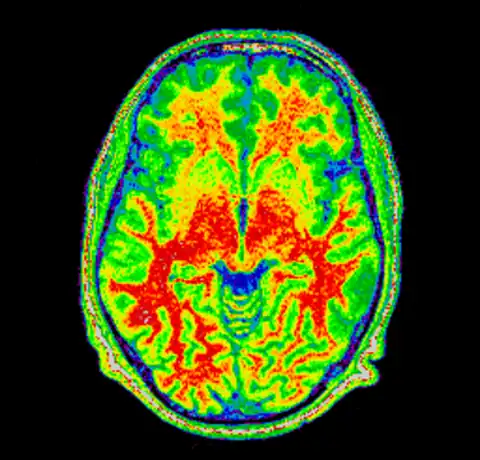

And then produce an image of it using the Spectral colormap

mincpik -scale 2 field.mnc -slice 150 -lookup -spectral field.png

And then for completeness sake, here are the original and corrected image using a spectral colormap to better visualise the change. Note that in the second (corrected) image the intensity of the white matter is more uniform (the red part).